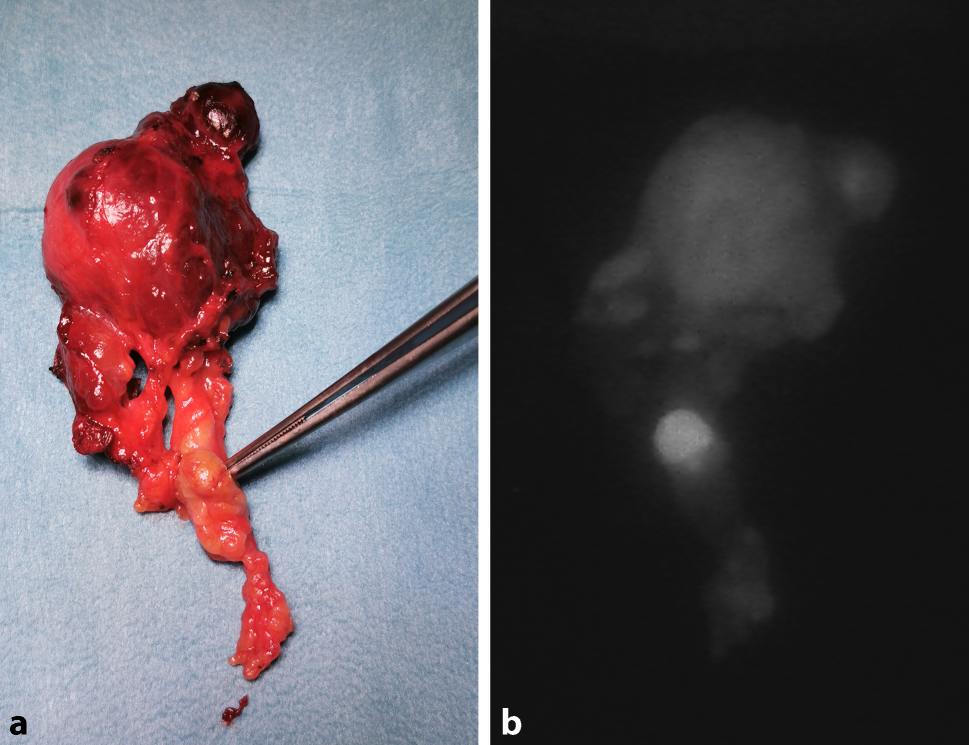

Bei Nichtauffinden einer Nebenschilddrüse im OP-Situs ist allerdings das resezierte Schilddrüsenpräparat im Kapselbereich mikrochirurgisch zu dissezieren, um unbeabsichtigt entfernte Nebenschilddrüsen zu entdecken und einer Autotransplantation zuzuführen. Vor allem ist die Begutachtung des Präparats am OP Tisch bei en bloc Thyreoidektomie mit zentralem Lymphknotenkompartement wichtig, da darin Nebenschilddrüsen verborgen sein können. Bei der Problematik der Nebenschilddrüsendarstellung kommt in Zukunft die vielversprechende Methode der Autoimmunfluoreszenzdarstellung auf uns zu, wobei man sich die Eigenschaft der Nebenschilddrüsen zunutze macht, bei Beleuchtung mit definiertem Laserlicht zu fluoreszieren und so mit einer speziellen Kamera sichtbar zu werden (Abb. 9a,b; [48, 49]). Zusätzlich kann man durch intraoperative Injektion von ICG (Indocyaningrün) auch die Durchblutung der Epithelkörperchen prüfen [5052]. Die korrekte Technik der Autotransplantation setzt ein Morcellement der Nebenschilddrüse in möglichst kleine Fragmente voraus, da das Nebenschilddrüsengewebe anfänglich nur durch Diffusion ernährt wird und diese erreicht nur 6 Zelllagen. 80 % der korrekt autotransplantierten Nebenschilddrüsen produzieren langfristig wieder Parathormon [53].

Abb. 9

a Schilddrüsenpräparat en bloc mit zentralen Halslymphknoten: unbeabsichtigt mitentfernte Nebenschilddrüse (Pinzette). b Die Autofluoreszenzdarstellung zeigt das unbeabsichtigt mitentfernte Epithelkörperchen: eine hoffnungsvolle Technologie zur Vermeidung des Hypoparathyreoidismus